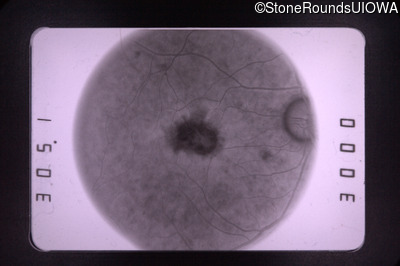

Fluorescein Angiography - Right - 20/70 -1 cc

Exemplar